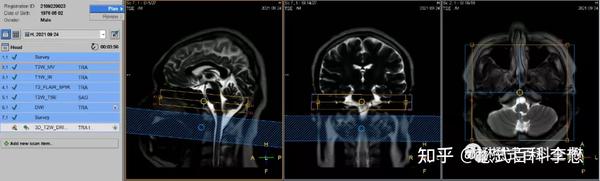

Mri Scans Magnetic Resonance Imaging And Mri Scan With Contrast